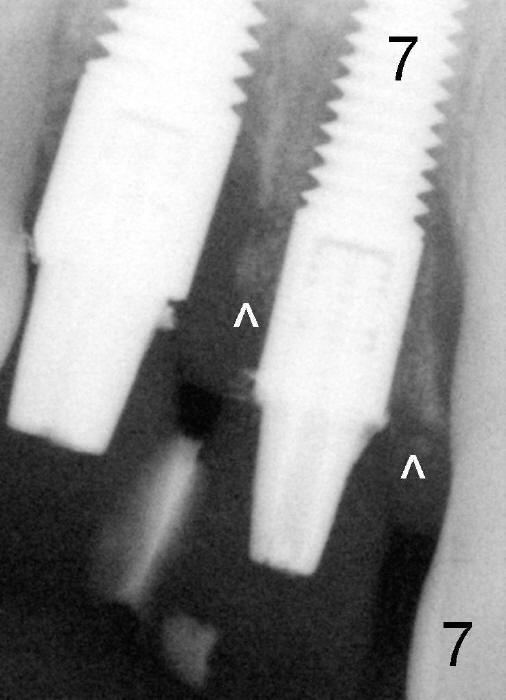

Fig.7: One and a half months postop. ^: bone graft.